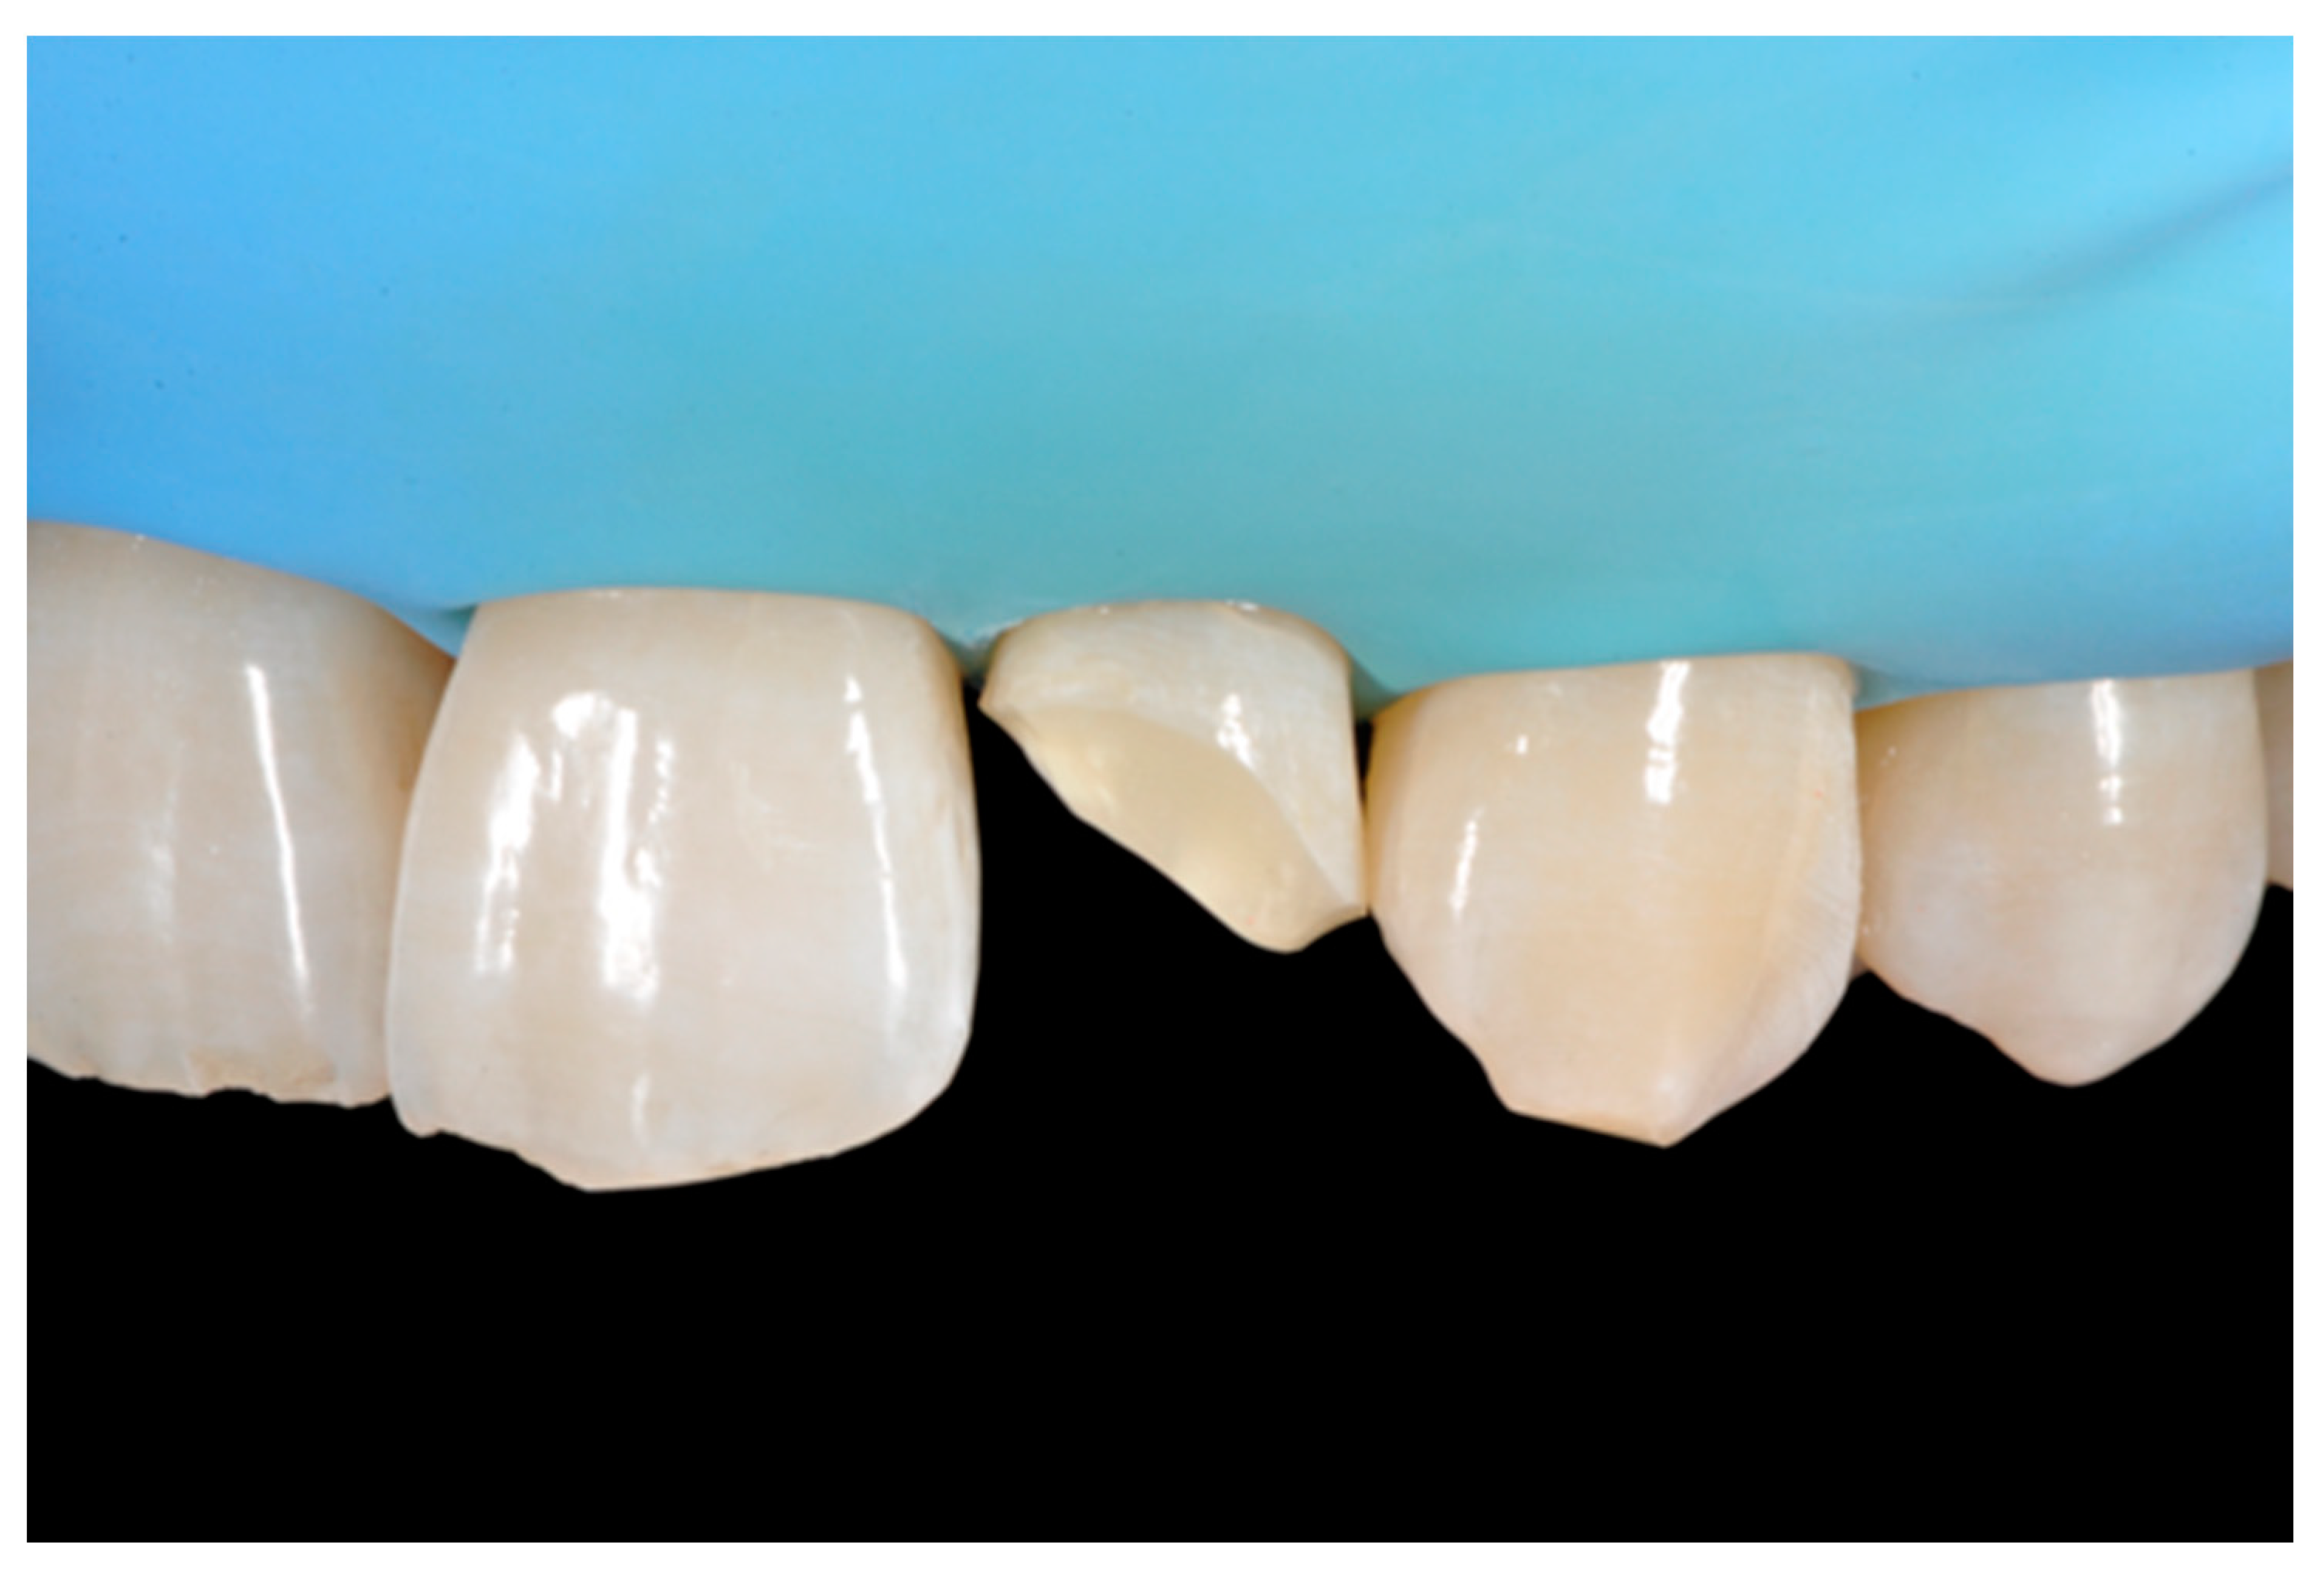

A healthy 38-year-old man referred to the dental office for the esthetic rehabilitation of left central maxillary incisor (Figure 41). Shade was selected as described in previous cases, using the button-try technique [14]. Isolation, preparation (Figure 42) and adhesive procedures were performed (Tokuyama Bond Force, Tokuyama Dental, Osaka, Japan). and Class III was restored on right central incisor (Asteria, A2B, Tokuyama Dental, Osaka, Japan). Frame was then completed on #2.1 (Figure 43) with the use of posterior sectional matrices using translucent and body material (Asteria, NE, A2B Tokuyama Dental, Osaka, Japan). After removing excesses both from the incisal margin and from the interproximal portion (Figure 44) silane and adhesive was applied strictly following the procedure described in Section 2.1.2. Dentinal body (Asteria, A2B, Tokuyama Dental, Osaka, Japan) was applied to reproduce internal anatomy (Figure 45) and then the external translucent enamel (Figure 46) (Asteria, NE, Tokuyama Dental, Osaka, Japan) was applied. The restoration shows good integration 6-months post-operative (Figure 47).

Figure 41.

Initial clinical situation.